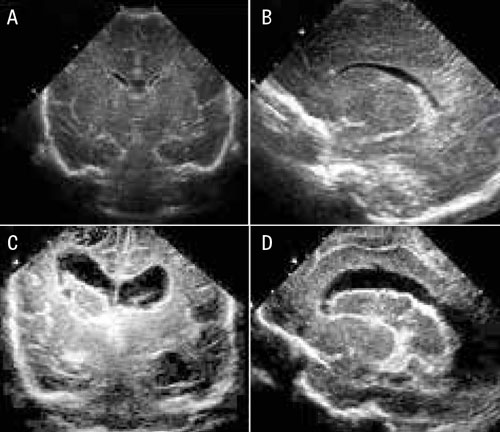

Utbredningen av blödningen ligger till grund för en stadieindelning, som har prognostisk betydelse. Grad I-blödningar är begränsade till germinalmatrix, medan blödningen vid grad II bryter igenom ependymet och blod kan visualiseras i sidoventrikeln. Vid grad III täcker den intraventrikulära blödningen >50 procent av den vid ultraljud visualiserade ventrikel­ytan (Figur 3). Grad IV definieras bättre som en periventrikulär hemorragisk infarkt och utgörs av blödning lokaliserad i ischemisk periventrikulär hjärnvävnad. I kliniska studier kategoriseras grad III och periventrikulär hemorragisk infarkt som svår intraventrikulär hjärnblödning och har dyster prognos; 40–80 procent av överlevande barn utvecklar posthemorragisk ventrikeldilatation/kognitiv funktionsnedsättning och/eller cerebral pares.

Figur 3. Bilder från ultraljud av hjärna hos för tidigt födda barn. A) koronarsnitt, normal hjärna; B) sagittalsnitt, normal hjärna; C) koronarsnitt, dilaterade sidoventriklar med intraventrikulär koagelbildning; D) sagittalsnitt, dilaterade sidoventriklar med intraventrikulär koagelbildning.